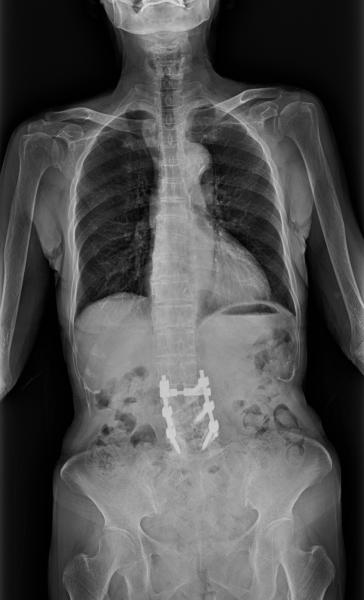

Contrast agents improve every kind of medical image from computed tomography (CT) to magnetic resonance imaging (MR) ...